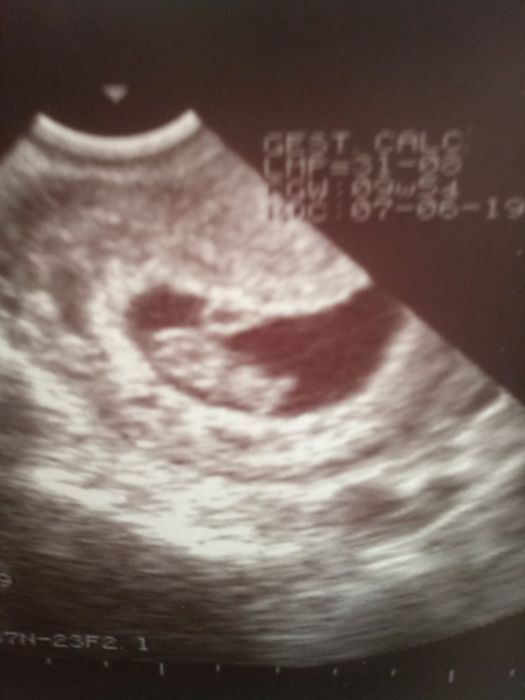

Tak holky kontrola proběhla v pořádku. Prcek se má cíle k svetu:) dnes jsem dle utz 9+2. Objednala jsem se už na ten prvotní screening a překvapilo mě, že je to na 2x. Mám přijet vezmou mi krev a změří plod a za 3 tydny pojedu na velký utz.

ENID to sú skvelé správy

gratulujem a máš krásnu fotku